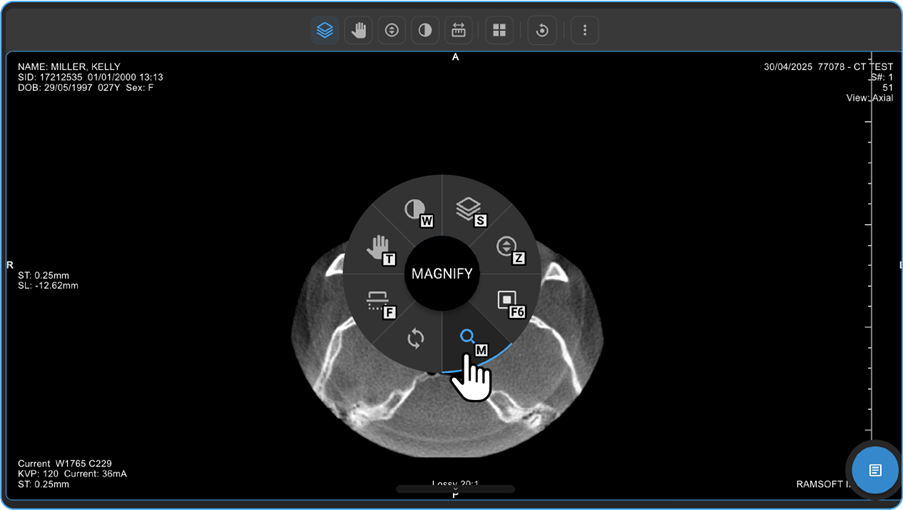

• Zoom & Magnify

1. On the Blume Homepage, go to the Completed Studies, open the desired study, and click View Images.

2. On the image viewer, Right-click anywhere on the study image to open the adjustment wheel.

3. You can locate the looking glass icon on the lower side of the wheel. When you hover the cursor over the icon, it brightens in Blue, and you can see the name "Magnify" in the middle of the wheel.

vai

1. Select the Magnify option.

2. Hold the left mouse button and move the mouse in desired directions over the image to see the magnified view of the part/region of the image.